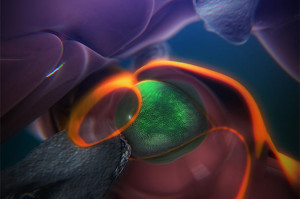

- A still from an animation that shows the steps of how blood stem cells take root in the body of a zebrafish to generate blood. (Credit: Boston Children’s Hospital/Stem Cell Research Program)

A see-through zebrafish and enhanced imaging provide the first direct glimpse of how blood stem cells take root in the body to generate blood. Reporting online in the journal Cell, researchers in Boston Children’s Hospital’s Stem Cell Research Program describe a surprisingly dynamic system that offers several clues for improving bone-marrow transplants in patients with cancer, severe immune deficiencies, and blood disorders, and for helping those transplants “take.”

The steps are detailed in an animation narrated by senior investigator Leonard Zon, director of the Stem Cell Research Program and professor of stem cell and regenerative biology at Harvard Medical School.